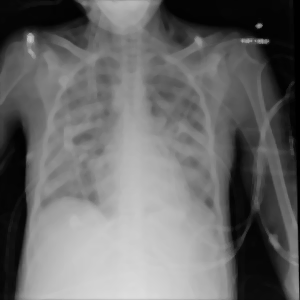

Yuklangan rasm